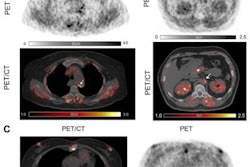

Contrast-enhanced CT (ceCT) and FAPI-PET/CT (68Ga-FAPI-PET) images from the same patient with local disease recurrence. In contrast to CT, FAPI-PET/CT discriminates a metastatic lymph node from the local recurrence mass (red arrow). FAPI-PET/CT also reveals possible new liver (yellow arrows) and bone (blue arrows) metastases. Images courtesy of Journal of Nuclear Medicine."In all cases, changes in staging were caused by the detection of new or additional distant metastases in one or more organ systems," the authors added. They also found a "markedly elevated uptake" of Ga-68-FAPI in most PDAC patients as soon as one hour after administration.

The findings suggest that Ga-68-FAPI- PET/CT is a "promising new imaging modality in staging of PDAC that may help to detect new or clarify inconclusive results obtained by standard CT-imaging," Röhrich and colleagues concluded.

"Analyses of tracer biodistribution demonstrated a high FAPI uptake in primary PDAC as well as lymph nodes and distant metastases, whereas healthy tissues have negligible background activity," they wrote. "This leads to excellent tumor/background ratios for PDAC, similar to those shown by previous studies on FAPI-PET/CT in PDAC and other tumors."